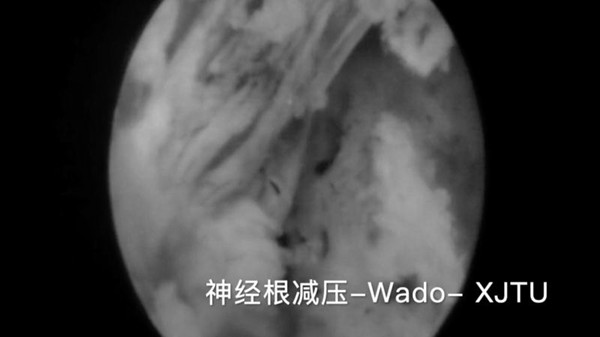

术中脊髓神经根得到充分减压

与传统的腰椎后路开放减压手术及通道下的MIS-TLIF手术相比,经脊柱内镜后路腰椎ENDO-TLIF/PLIF手术,创伤更小,神经根及硬膜囊显露清晰,且最大限度的保护了脊柱骨骼、韧带及肌肉的完整性,对脊柱运动单元稳定性影响较小,术后患者感受更佳,康复更快,脊柱的ENDO-LIF微创手术必将成为未来的发展趋势。